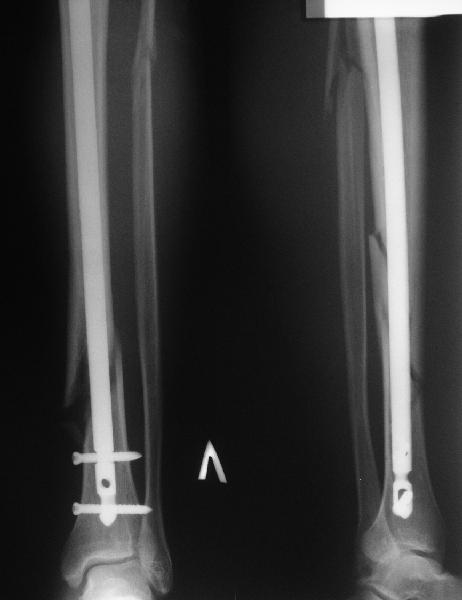

Все наши сомнения связаны с тем, что этих незначительных погрешностей (небольшой вальгус, неглубоко пробит гвоздь, мало запирающих винтов в

дистальном отломке) не одна, а несколько, и вместе они могут значительно осложнить дальнейшую жизнь пациенту. В нашей практике были подобные случаи, при которых после разрешения полной нагрузки либо начинала увеличиваться деформация, либо происходил перелом гвоздя по ближайшему отверстию. Кроме того, при диафизарных переломах, имея в арсенале надежный фиксатор, нет никакой необходимости вынуждать пациента ограничивать нагрузку на ногу в течении 2-3 месяцев.

Взвесив все <<за>> и <<против>>, мы приняли решение и выполнили реостеостинтез: выбили гвоздь до линии перелома, провели отклоняющую

спицу, забили обратно гвоздь и заблокировали внизу 3-мя винтами, вверху одним. Вся операция заняла меньше часа. Сегодня пациент ушел от нас домой с полной нагрузкой на ногу.